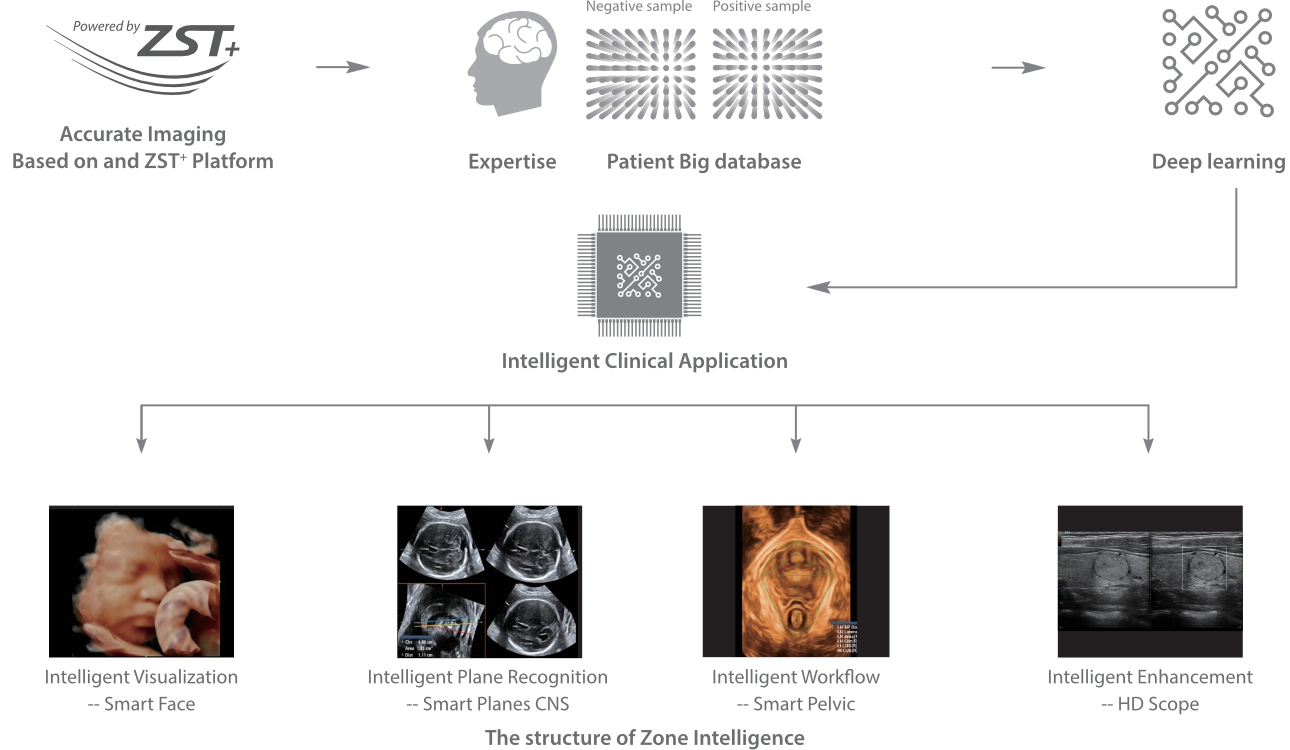

con Zone?Intelligence

Desde que se fund├│ la compa?├Ła, Mindray ha explorado incansablemente nuevas formas de mejorar la confiabilidad del diagn├│stico. Con la revolucionaria tecnolog├Ła de ZONE Sonography?, la nueva plataforma ZST+ de Resona?7 lleva la calidad de la imagen por ecograf├Ła a un nivel superior mediante el procesamiento de datos de canal y la adquisici├│n de zona.

Adem├Īs de la calidad de imagen de primer nivel, Resona?7 tambi├®n mejora las capacidades de investigaci├│n cl├Łnica con el revolucionario V?Flow para la evaluaci├│n hemodin├Īmica vascular y con la adquisici├│n de planos m├Īs inteligente a partir de conjuntos de datos 3D para el diagn├│stico del SNC fetal. Al combinar el funcionamiento multit├Īctil basado en gestos m├Īs intuitivo y todas las caracter├Łsticas cl├Łnicas esenciales, Resona?7 realmente lidera las novedades en innovaci├│n de ecograf├Łas.